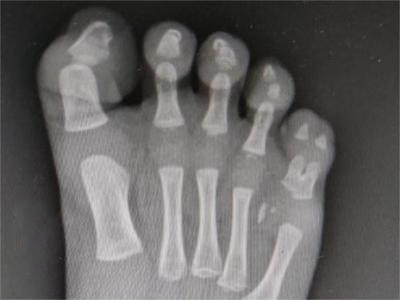

并趾畸形症状图片

并趾畸形是指遗传、宫内机械因素、胚胎发育异常、神经和肌肉功能缺陷等因素作用下,导致两个或两个以上足趾部分或全部组织成分相连,部分可同时伴有骨组织连接,临床可以通过手术方式进行治疗。

并趾畸形患者两个或两个以上足趾部分或全部组织成分相连,完全相连着称为完全性并趾,伴有骨组织连接者称为复杂性并趾。